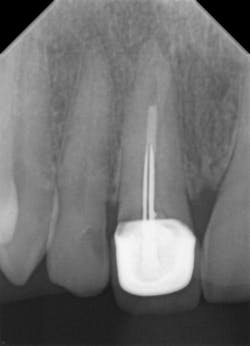

The resolution of DentiMax Open sensors provides 14-16 lp/mm actual, 25 line lp/mm theoretical on size 0 sensor and >20 lp/mm actual, 25 line lp/mm theoretical on the size 1, 1.5, and 2 sensors. Further, Dr. Gordon J. Christensen’s Clinicians Report says that “DentiMax’s sensors exhibited excellent resolution, sensitivity, image quality, and exposure latitude in controlled comparisons with other leading sensor brands.” Quality images are the result with bitewings (figure 9), anterior periapicals (figures 10 and 11), and posterior periapicals (figure 12).